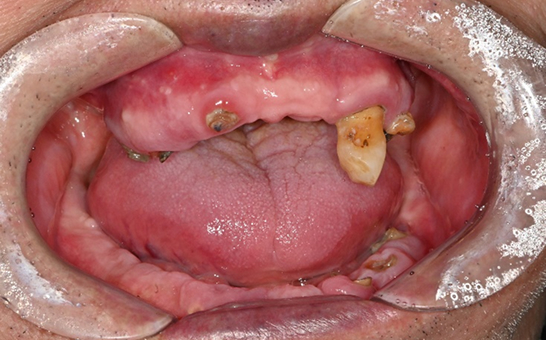

바른선택치과의원 전악 임플란트

치료 시작 전 촬영 2024.01.24 | 치료 완료 후 촬영 2024.12.26

CASE 01 김** / 60대

전악임플란트

1 예후불량 치아 발치

2 발치 후 즉시 임플란트 식립 및 뼈이식

3 고정성 보철물로 수복 후 일상 회복